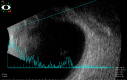

Retinitis pigmentosa can be associated with exudative vasculopathy in rare instances, which can manifest as retinal vasoproliferative tumours. We present the case of a 33-year-old woman previously diagnosed with retinitis pigmentosa sine pigmentosa in both eyes. She was asymptomatic and just came in for a routine follow-up eye examination. Thorough examination of the peripheral retina on the right eye revealed a dome-shaped retinal tumour with a feeder vessel and surrounding exudative changes at the superotemporal periphery, consistent with a secondary retinal vasoproliferative tumour from retinitis pigmentosa. She subsequently underwent focal laser photocoagulation of the tumour which resulted in tumour stabilisation. While exudative vasculopathy is very uncommon in retinitis pigmentosa, ophthalmologists need to be aware of its occurrence in such patients. Vision loss may occur from exudation, haemorrhage, retinal detachment and neovascularisation. A thorough examination of the peripheral retina is warranted in these cases.